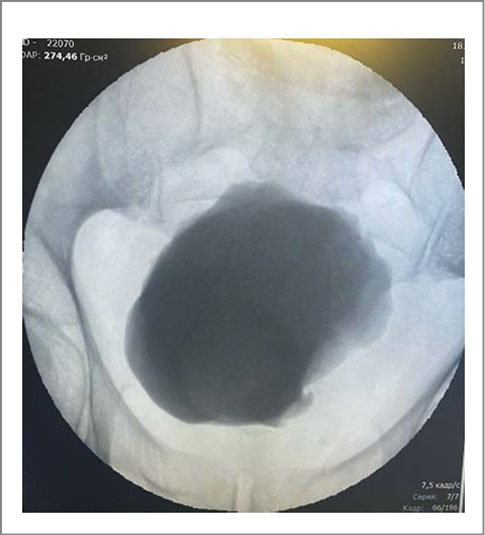

Наряду с ДМП выявлена аномалия в виде аплазии левой почки. В правой почке определена простая субкапсулярная киста объемом 15 см3. Объем предстательной железы составил 18,2 см3. При урофлоуметрии максимальная скорость мочеиспускания равнялась 15,0 мл/с, средняя – 8 мл/с при объеме мочеиспускания 210 мл. В перечень выполненных исследований вошли КТ живота и таза с контрастированием, микционная цистография и фиброуретроцистодивертикулоскопия. При последнем исследовании устье левого мочеточника не выявлено (рис. 3–6).

Рис. 5. Пациент В., микционная цистограмма, ДМП.

Послеоперационный период протекал гладко. Цистостомический дренаж удален на 3-и сутки, уретральный катетер – на 12-е. После удаления катетера самостоятельное мочеиспускание восстановилось. Урофлоуметрия: максимальная скорость мочеиспускания – 16,0 мл/с, средняя – 9 мл/с. При УЗИ мочевого пузыря: объем мочевого пузыря 350 мл, остаточной мочи нет. По данным ретроградной цистографии затеков не выявлено (рис. 8).

Рис. 8. Пациент В., цистограмма на 8-й день после лапароскопической дивертикулэктомии (отсутствие затеков).